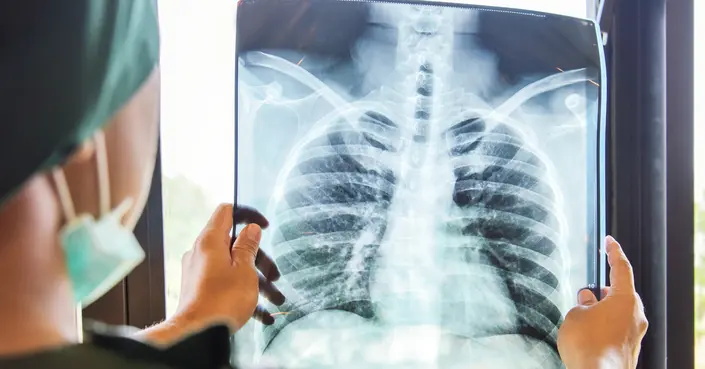

السل هو مرض بكتيري تسببه بكتيريا المتفطرة السلية (Mycobacterium tuberculosis). ينتشر المرض من شخص لآخر عبر الهواء عندما يسعل أو يعطس الشخص المصاب بالسل الرئوي النشط. هذه القطرات الصغيرة المحمّلة بالبكتيريا يمكن أن يستنشقها الآخرون، مما يؤدي إلى انتقال العدوى.

على الرغم من أن السل يصيب الرئتين في الغالب، إلا أنه يمكن أن ينتقل عبر مجرى الدم ليصيب أعضاء أخرى في الجسم، بما في ذلك الكلى والعظام والدماغ. في الماضي، كان السل مرضًا قاتلاً، ولكن بفضل التقدم في الطب، يمكن علاج معظم الحالات بنجاح باستخدام دورة مكثفة من المضادات الحيوية تستمر عادةً لعدة أشهر.